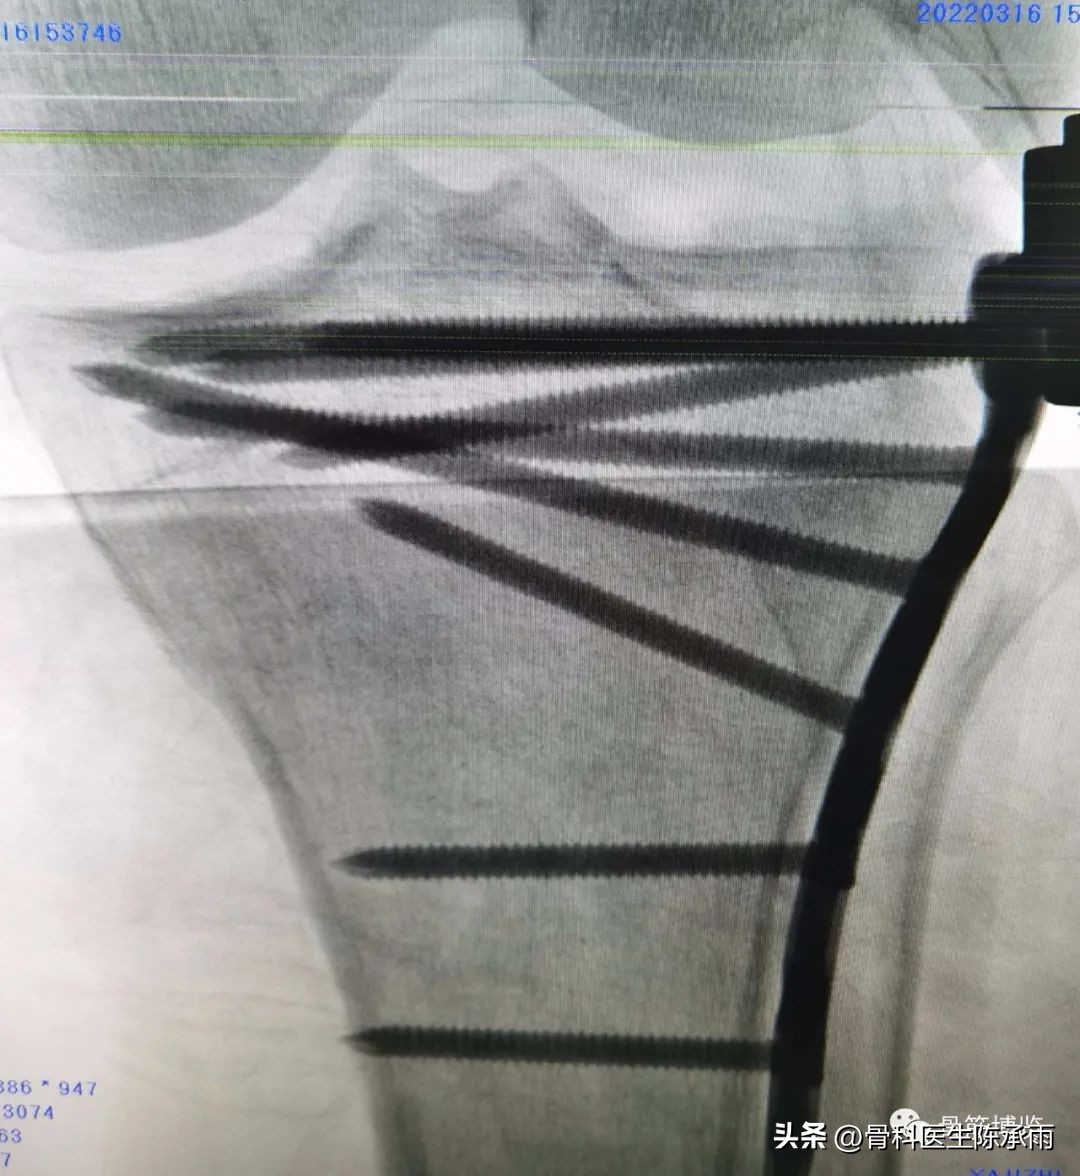

1例

2例

3例

4例

5例

6例

7例